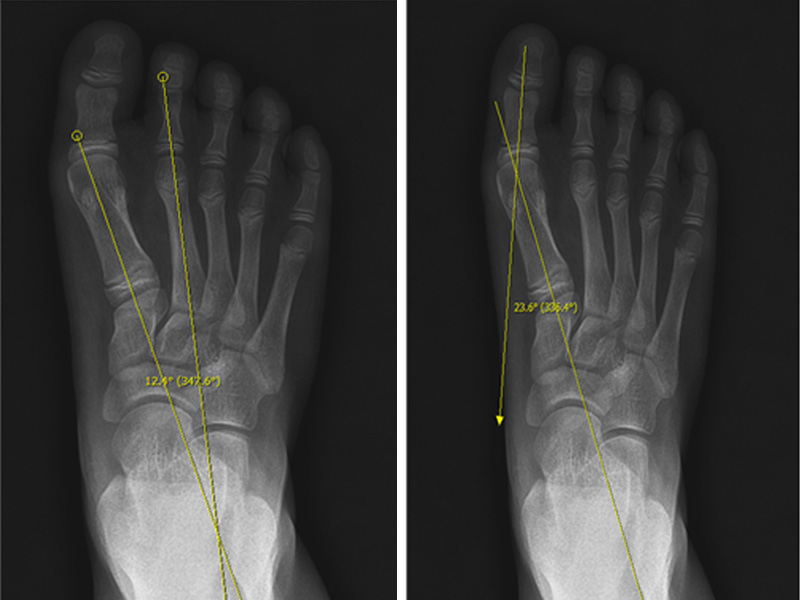

아킬레스 짦음증이 있는 아이들은 자주 발목이나 종아리가 아프다고 하며, 아픈 부위를 특정하지 못하고 다리가 아프다고 하며 내원합니다. 가끔은 발 뒤꿈치를 들고 걷는다고 하거나 까치발로 걷는다고 내원하기도 합니다. 걷는 자세는 주로 팔자걸음에 상체를 흔들면서 걷습니다. 이런 아이들은 좀 더 크면 무릎이나 허리를 아파하기도 합니다. 어린아이들의 경우에는 X-ray 등에도 이상 소견이 보이지 않아 주로 성장통이라고 오진을 받기도 합니다. 저희 병원에서는 현재 이에 대한 연구를 진행하고 있으며, 이런 아이들의 대략 60% 정도에서 비만이 있고, 이러한 비만아이들은 골연령이 약 1.5세 정도 증가하게 되어 성인예측키에서 약 3~4cm 정도의 손실이 발생합니다. (이상은 본원에서의 미발표 연구결과입니다)